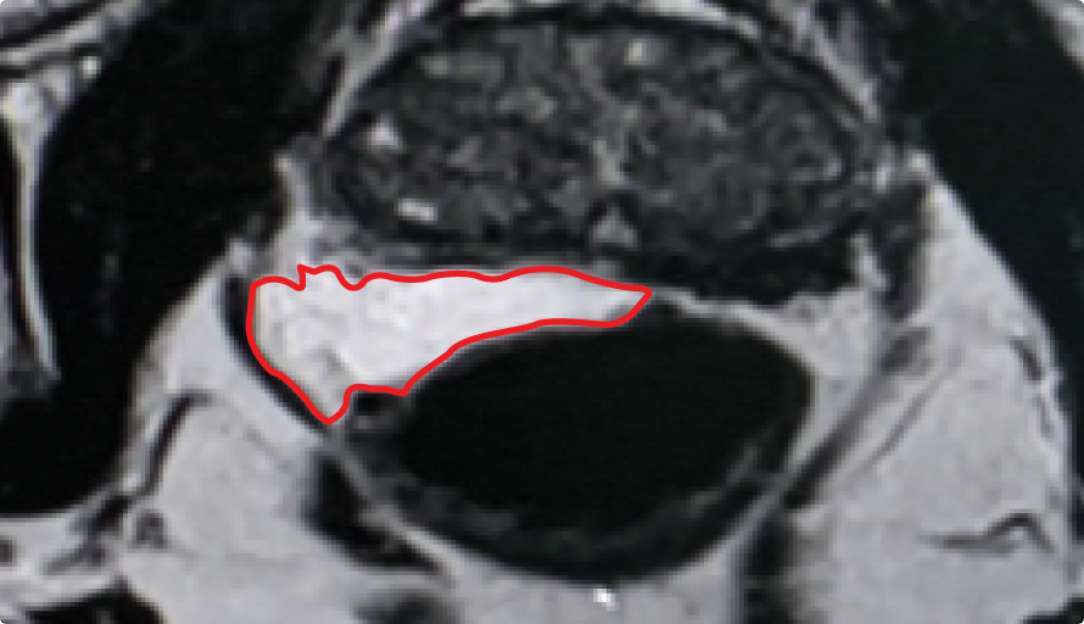

BARRIGEL

Implant Symmetry RESULTS6 >95%

Pivotal Trial Patients; % of implants centered on prostate midline

PEG HYDROGEL

Implant Symmetry RESULTS7 >49%

First Barrigel Cases - Consecutive Patients (Same Day)

TRUS images courtesy of Daniel R. Welchons, MD

Urologist; New York, United States